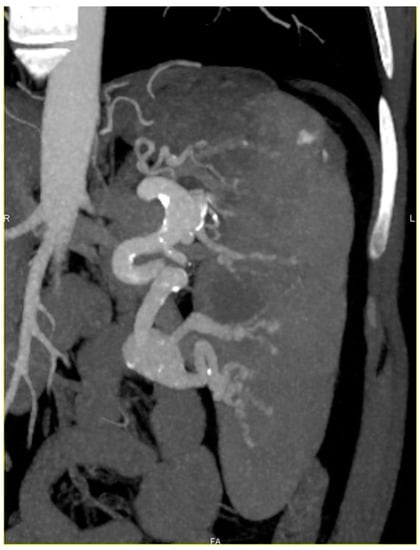

| 2 | F, 59 | 19 | N370S/84GG | ERT 16 U/kg eow | 49 | Complex set of four SAA |